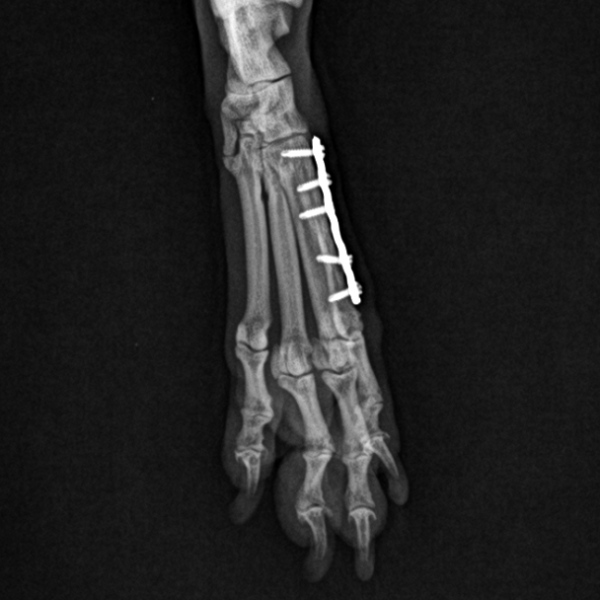

강아지 발허리뼈 골절 수술 진행

7e57501c3435cf47aec636df8f92d2a8_1771469717_9037.jpg

수술은 큰 문제 없이 무사히 마무리되었습니다.

강아지 골절 수술 이후 아이는 전반적인 컨디션이 안정적이었으며

점차 다리 사용이 자연스러워지는 모습을 보였습니다.

→ 수술 부위 또한 염증, 부종, 통증 반응 없이

양호하게 유지되고 있었습니다.

7e57501c3435cf47aec636df8f92d2a8_1771469740_5202.png

이후 재진 당일 시행한 방사선 검사에서도

플레이트·나사는 안정적으로 유지되고 있으며,

골 유합이 점차 진행되는 소견이 확인되었습니다.